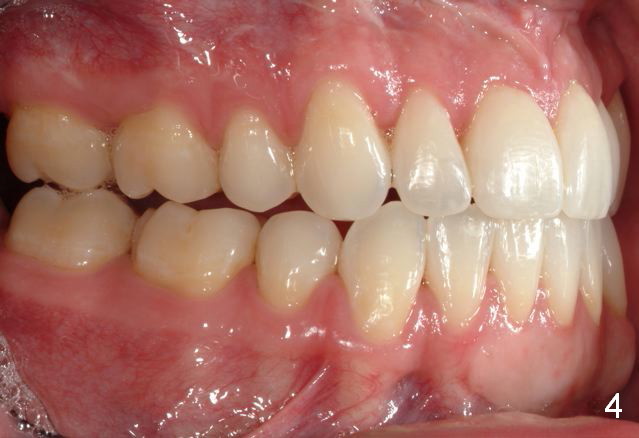

Final photos are taken on 03/23/2016. Mid face deficiency improved, now just a hint (Fig.3). Before (Fig.4,10) and after (Fig.5-9) occlusal adjustment of the canines.